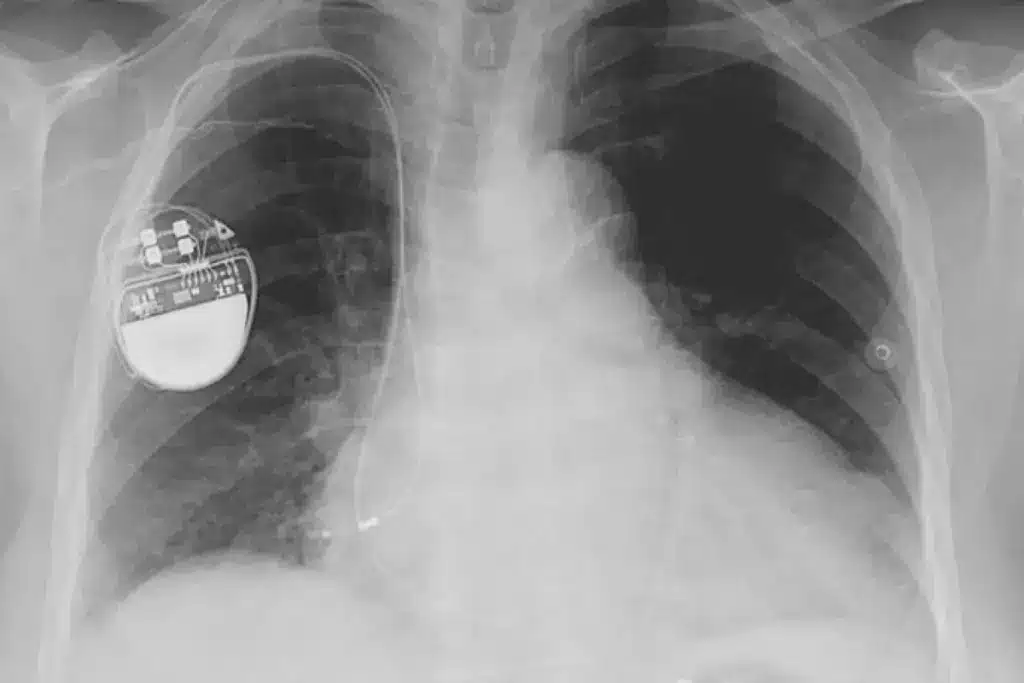

A pacemaker has two main parts: the pulse generator and the leads. The pulse generator is a small metal box with a battery and circuitry. It’s placed under the skin, near the collarbone.

The leads are thin wires that connect the pulse generator to the heart. They send electrical impulses to make the heart beat regularly.

The pacemaker implantation procedure is done under local anesthesia. This keeps the patient awake but without pain. A small incision in the chest allows the pacemaker leads to be placed in the heart using X-ray imaging.